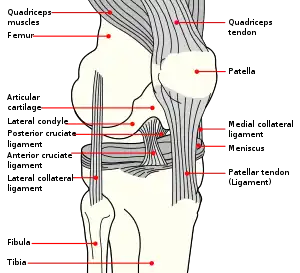

Anatomy of the knee

The patella is a triangular sesamoid bone that is embedded in tendon. It rests in the patellofemoral groove, an articular cartilage-lined hollow at the end of the thigh bone (femur) where the thigh bone meets the shin bone (tibia). Several ligaments and tendons hold the patella in place and allow it to move up and down the patellofemoral groove when the leg bends. The top of the patella attaches to the quadriceps muscle via the quadriceps tendon,[2] the middle to the vastus medialis obliquus and vastus lateralis muscles, and the bottom to the head of the tibia (tibial tuberosity) via the patellar tendon, which is a continuation of the quadriceps femoris tendon.[13] The medial patellofemoral ligament attaches horizontally in the inner knee to the adductor magnus tendon and is the structure most often damaged during a patellar dislocation. Finally, the lateral collateral ligament and the medial collateral ligament stabilize the patella on either side.[2] Any of these structures can sustain damage during a patellar dislocation.